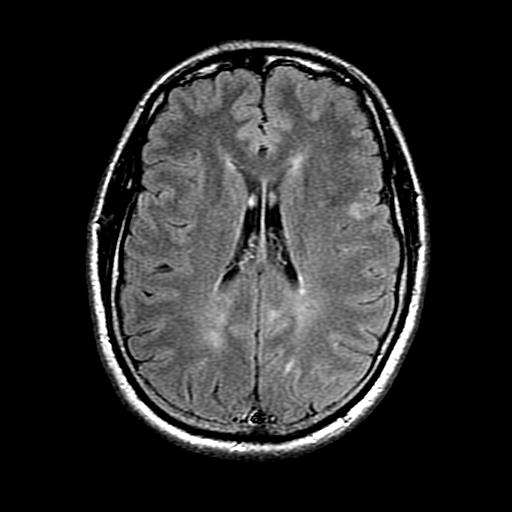

Dr Michiko Yoshie and her colleagues Professor Hugo Critchley, Dr Neil Harrison, and Dr Yoko Nagai were able to pinpoint the brain area that causes the performance mishaps during an experiment using functional magnetic resonance neuroimaging (fMRI).

In the new study, published in Scientific Reports, participants’ brain activity was monitored while carrying out a task that required them to exert a precise amount of force when gripping an object.”